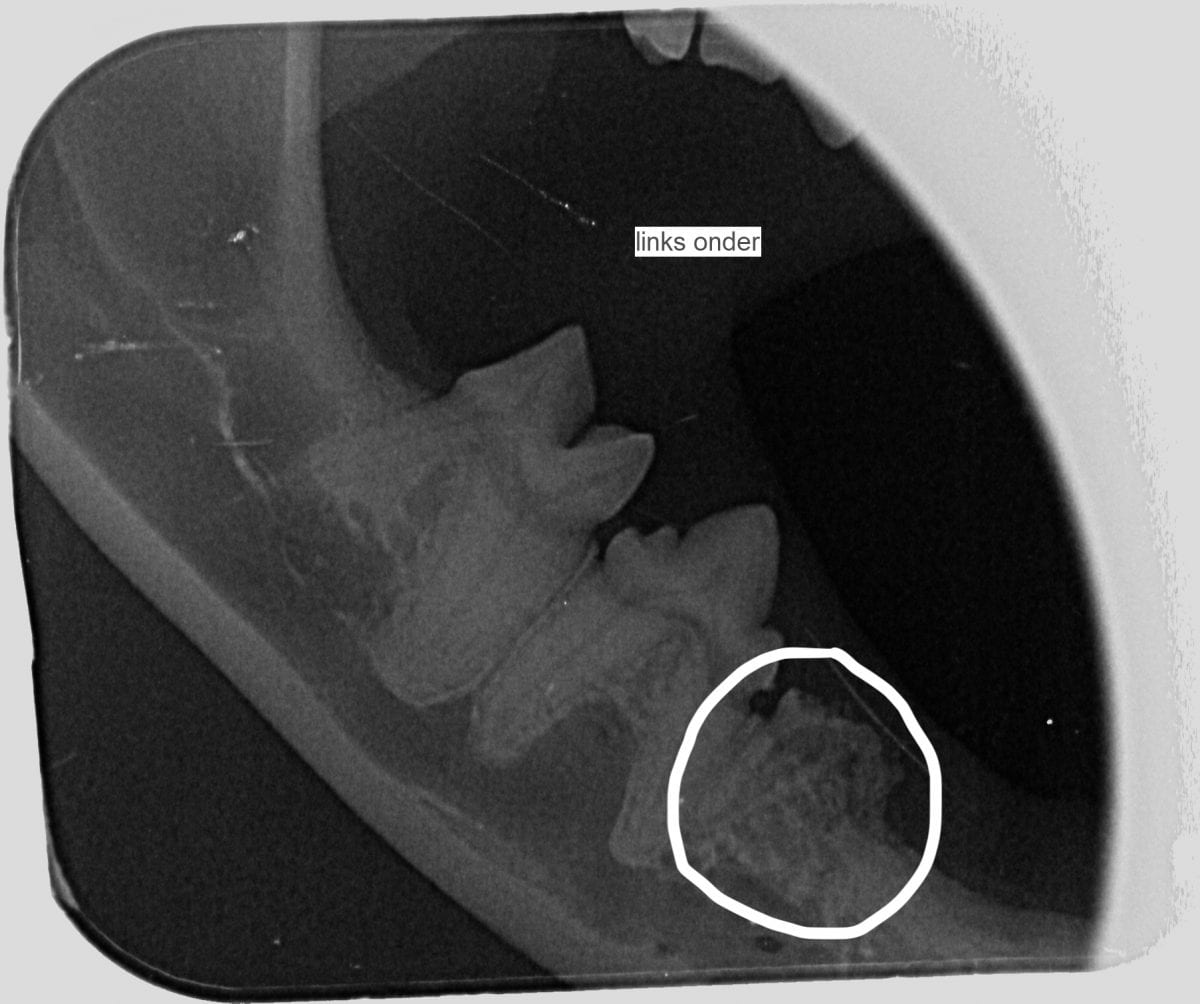

Onderaan deze pagina staan 2 dentale röntgenfoto’s. Op de eerste foto hieronder zie je een kies die al bijna helemaal opgelost is. De foto ernaast laat een kies zien waarbij de wortels nog aanwezig zijn.